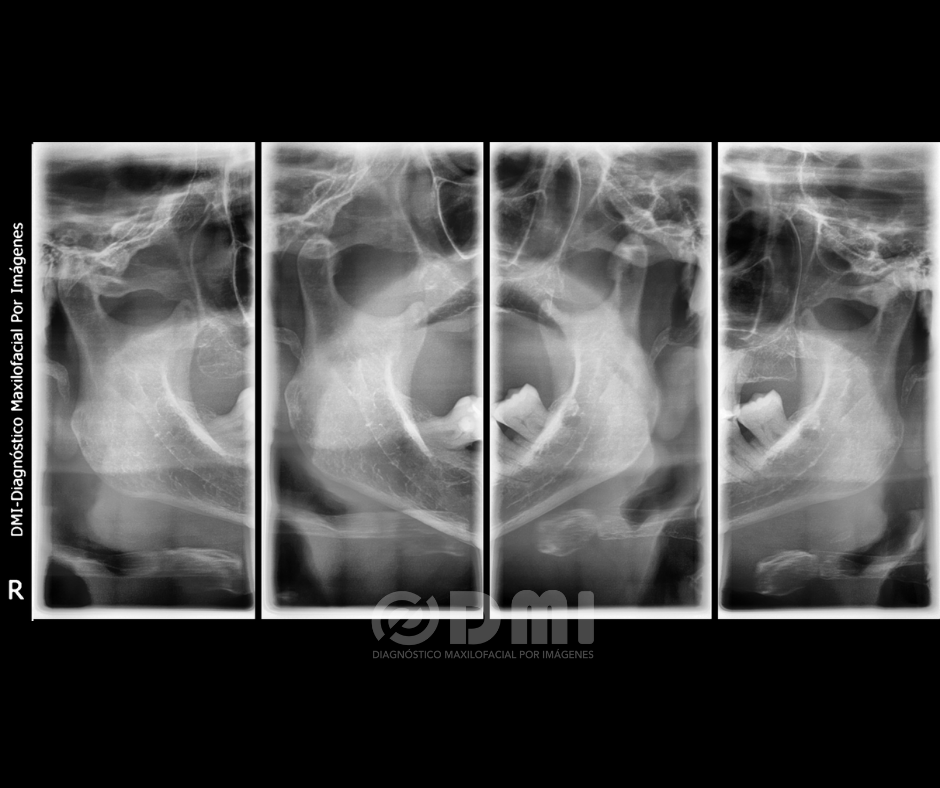

Al evaluar la radiografía comparativa de ATM; En máxima intercuspidación no es posible diferenciar correctamente el espacio articular de ambos lados, en máxima apertura es posible identificar discreta sobre extensión de la traslación condilar.